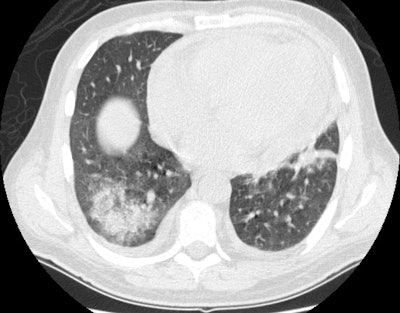

Wegeners: The patient shown in the case below presented with hemoptysis. CXR demonstrated cavitary areas of consolidation in the right mid and left upper lungs (Click CXR to enlarge image). Chest CT revealed cavitary nodules, cavitary areas of consolidation, and non-cavitary areas of patchy parenchymal consolidation. Patient was C-ANCA positive and lung biopsy revealed Wegener's. |

On CT, lung nodules/masses are the most common finding and are seen in 40-90% of patients [12,13,14]. The nodules are usually multiple, bilateral, 2-4 cm in size, usually random in distribution, subpleural (89% of patients), or peribronchovascular (41% of patients), and lack a zonal predilection [1,12,14,15]. Feeding vessels entering the nodular lesions are very commonly identified at CT and reflect the angiocentric nature of the disorder [7]. A CT "halo sign" (a rim of ground glass attenuation surrounding the nodule) may be seen due to surrounding hemorrhage in up to 15% of cases [7,12,13]. The "atoll sign" - a rounded area of consolidation with contral ground-glass attenuation- can also be seen [15]. Cavitation occurs in approximately 25% of nodules larger than 2 cm [12]- typically thick walled with an irregular inner margin [13] (other authors suggest cavitation can occur in up to 50% of nodules larger than 2 cm [15]). Nodules may regress and reappear spontaneously. With treatment, approximately 50% of the nodules resolve, 40% diminish in size, but leave residual damage, and 10% remain unchanged [13]. Pleural effusions are noted in 5-50% of cases, typically the result of pleural involvement.

Patchy focal or diffuse parenchymal consolidations and ground

glass opacities are found in 30-53% of cases and are usually due

to pulmonary hemorrhage. The opacities are generally random

or patchy in distribution [14], but bilateral perihilar and

peribronchovascular distributions are the most common [15]. The

infiltrates may be found to be cavitary by computed tomography.